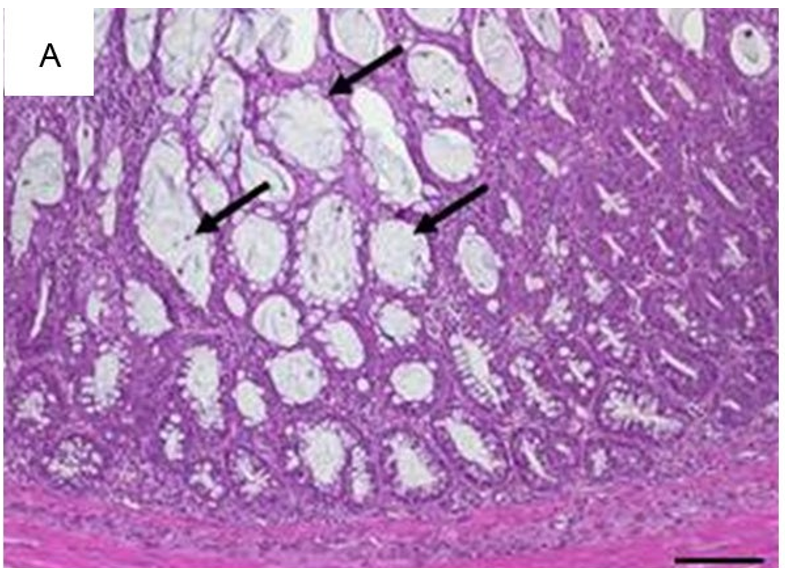

白细胞浸润固有层,这是所有肠炎模型的共有特征。尽管浸润了不同比例的嗜中性粒细胞、嗜酸性粒细胞、单核细胞、浆细胞和淋巴细胞,评估每高倍视野(HPF)组织内混合的炎症细胞,可充分反映了炎症相关的变化(图1A)。散在中性粒细胞是轻度浸润的典型特征(图1B)。从炎症细胞的主要局部粘膜定位开始(图1C),严重程度增加首先包括粘膜下层(图1D),随后延伸至固有肌层并最终导致透壁浸润(图1E)。最初见于上皮细胞层的主要变化包括隐窝上皮细胞增生,杯状细胞的损失,隐窝炎、隐窝脓肿和糜烂。

图1代表性HE染色的结肠切片图 说明了炎症细胞浸润的具体情况(A)横截面中浸润的混合白细胞(×400,比例尺20µm)